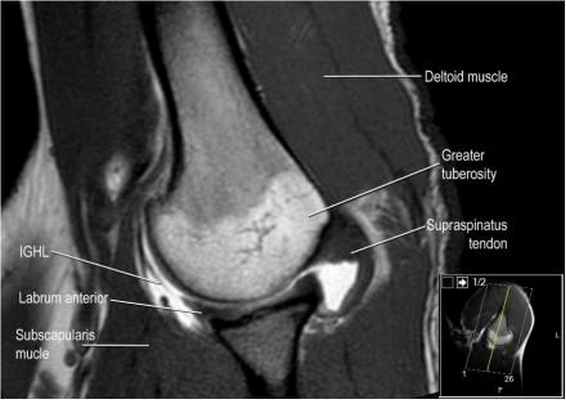

а бРис. 1. МР-артрография. МР-томограммы ПС: а – корональная плоскость, T1 TSE; б,в – аксиальная плоскость T1 TSE, FS T1 TSE

Протоколы нативного МР-исследования и МРА плечевого сустава включали получение трех взаимно перпендикулярных проекций (косой коронарной, косой сагиттальной и аксиальной). Нативное исследование проводилось с использованием следующих импульсных последовательностей: TSE PD SPAIR – изображения, взвешенные по протонной плотности, с эффектом подавления сигнала от жировой ткани; TSE_T1W-Т1 взвешенном изображении (ВИ) в режиме турбо-спин эхо; FFE_T2W-Т2 ВИ в режиме градиентного эхо (табл.1). МРА проводили в режиме TSE_T1W, а также с использования эффекта жироподавления – TSE_T1W SPIR (табл.2, рис.1). Исследование проводилось через 15 минут после введения контраста и выполнения пациентом маятникообразных движений верхней конечностью.

Изображение передних отделов плечевого сустава.

Сухожилие подлопаточной мышцы прикрепляется как к малому бугорку, так и к большому бугорку, давая поддержку длинной головке двуглавой мышцы в борозде двуглавой мышцы. Вывих длинной головки двуглавой мышцы плеча неизбежно приведет к разрыву части подлопаточной сухожилия. Манжета вращателей плеча состоит из сухожилий подлопаточной, надостной, подостная и малой круглой мышц.

Изображение задних отделов плечевого сустава.

Отображены надостная, подостная и малая круглая мышцы и их сухожилия. Все они прикрепляются к большому бугорку плечевой кости. Сухожилия и мышцы манжеты вращателей участвуют в стабилизации плечевого сустава во время движения. Без манжеты вращателей головка плечевой кости частично сместилась бы из суставной впадины, уменьшив силу отведения дельтовидной мышцы (мышцы вращательной манжеты координирует усилия дельтовидной мышцы). Повреждение манжеты вращателей может привести к смещению головки плечевой кости кверху, в результате вызвая высокое стояние головки плечевой кости.